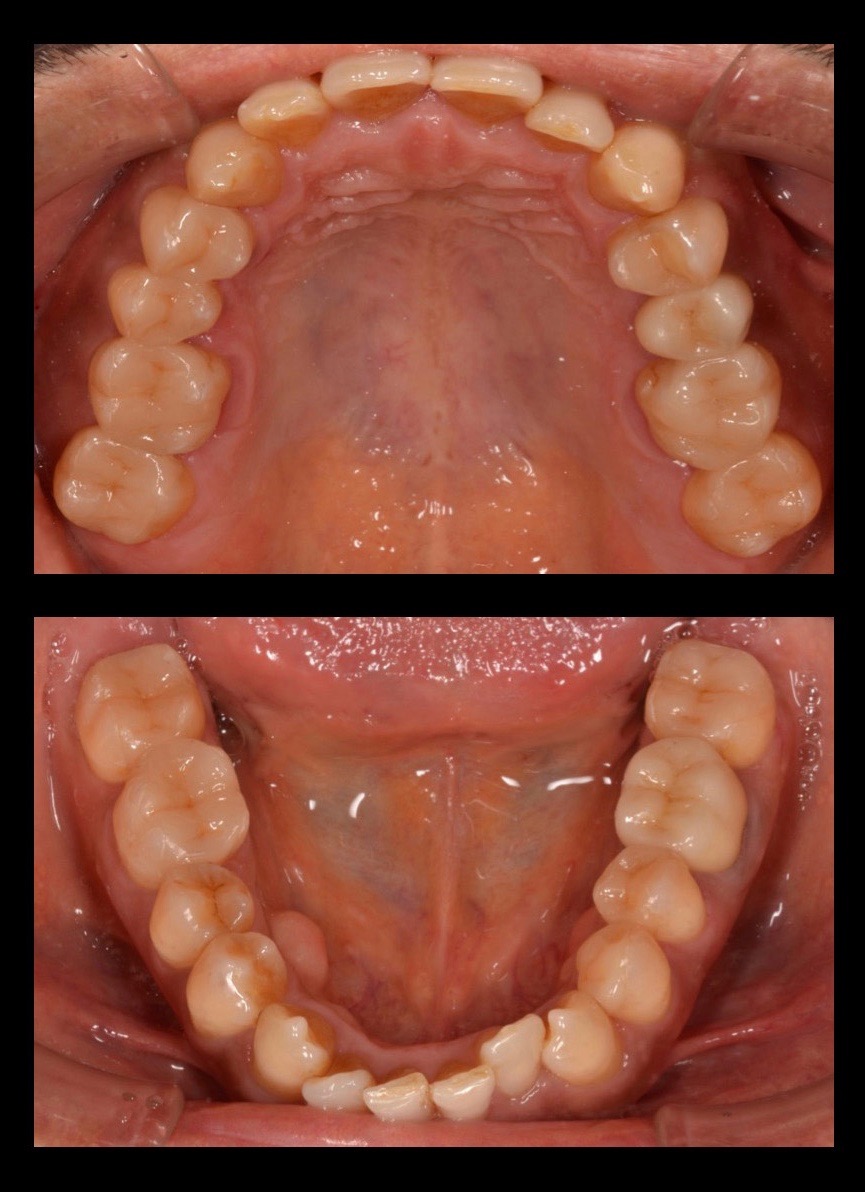

★メタルフリー治療

50代男性の、銀歯をなくしたいというご要望の症例です。レントゲンで発見された銀歯の下の虫歯を治療し、金属アレルギーのリスクもないセラミックで補綴。治療期間は2週間の短期間で、口の中が非常にスッキリした。味覚が良くなり食事が楽しみになったとのこと。

| リスク・副作用 | 治療終了後のメンテナンス不足による歯周病 歯ぎしりや過剰な噛み締めによるセラミックスの破折 |

|---|---|

| 費用 | 10万円/1本(税別) |

| 期間 | 2週間 |